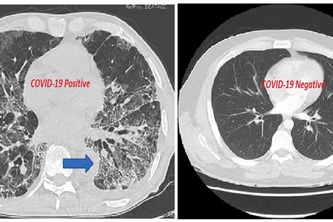

Chest CT scan image of a coronavirus infected patient showed distinctive hazy patch on outer edges of lungs. Using typical hazy patch as a feature pattern for training our AI based algorithm.